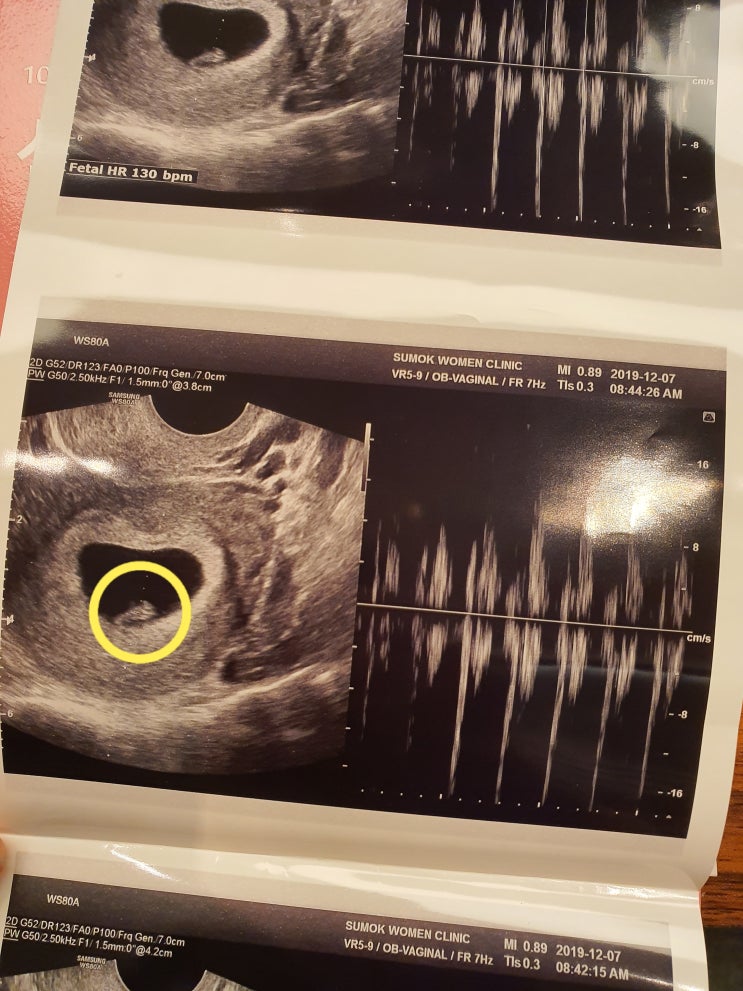

[임신6-7주] 입덧, 몸의 변화 그리고 심장소리 확인!

하잉하잉 오늘로 벌써 임신7주3일차입니다 임신6주전까지는 몸에 별다른 변화는 없다가 6주에 접어드니까 ...